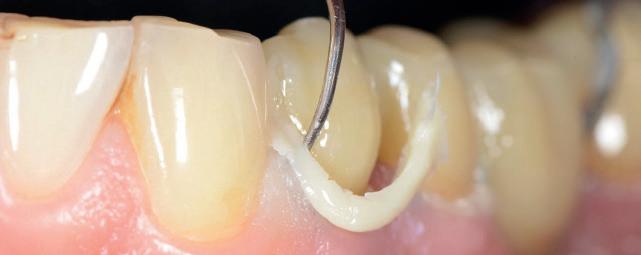

This innovative owable composite transforms shade matching into an effortless process—no shade guide required. With just two complementary shades, U and UD, it seamlessly blends with the surrounding tooth structure. Its easy polishability and long-lasting high gloss enables you to create beautiful, natural-looking restorations with minimal effort. And with strength comparable to many paste-type composites, it’s suitable for a wide range of clinical applications.

FLOWABILITIES

Low and Super Low for a wide range of indications 150 IMPRESSIVE STRENGTH

Sufficient for use even in stressbearing posterior restorations

Covers all VITA* shades in all cavities, except those lacking of a back wall of shade B3 and darker